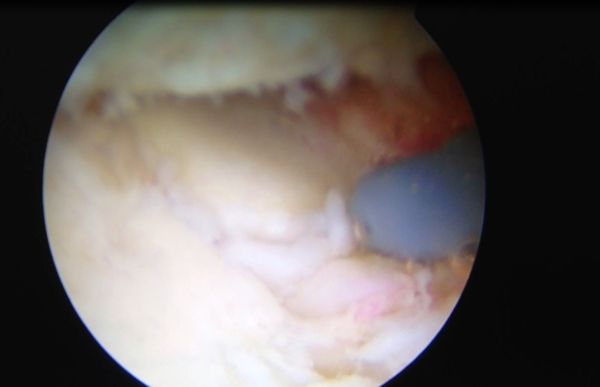

一般来说:1、对于疾病早期的患者,我们一般推荐休息、口服非甾体消炎药、理疗、康复治疗。2、对于保守治疗三个月效果欠佳的患者,我们一般根据患者的具体情况采用肘关节关节镜镜微创手术或小切口切开手术的方法来为患者解决问题。有的患者我们采用人工肘关节置换手术的方法帮助患者解决肘关节伸屈受限的问题。3、我们非常重视手术后的康复治疗。我们有专门的骨关节康复师和肘关节手术后全套的康复方案帮助患者早日康复。

上图:高绪仁医学博士、博士后、副主任医师、副教授在为肘关节僵硬、伸不直、屈不下来的患者进行肘关节关节镜微创手术治疗。